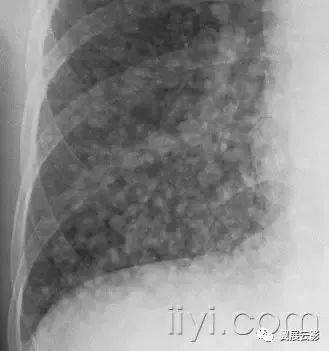

三十八、粟粒样

平片和CT:在胸片上,粟粒样代表大量小的、分散的、圆形肺部阴影(直径小于3mm),大小相对均以一致,双肺内弥漫性分布。是结核或者转移性病变弥漫性分布的特征。薄层CT上显示为广泛、随机分布的微结节。